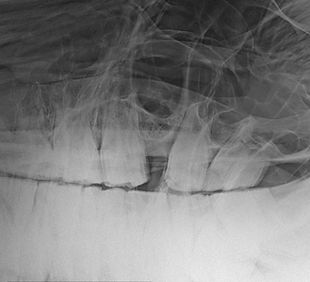

EQUINE DENTISTRY...

... has been the focus of my veterinary work since 2011. I place particular emphasis on dealing with the animal empathetically, with a view to its overall health. A high level of expertise with a constant out-of-the-box perspective is important to me. Since the horse's body must always be viewed as a unit, I am happy to work with your veterinarian, farrier or physiotherapist.